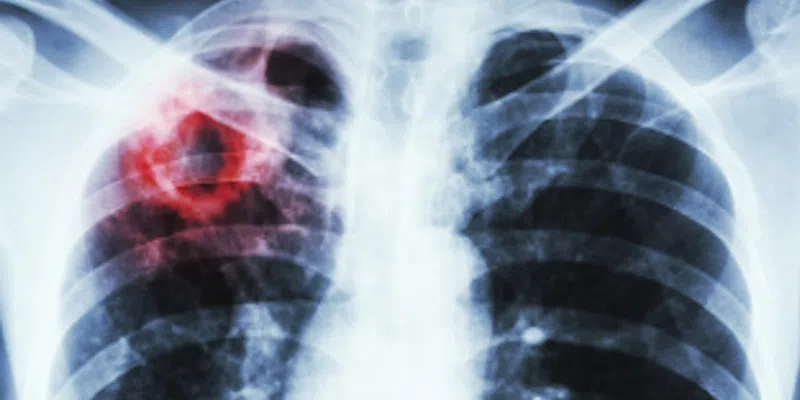

According to NL Health Services, TB is a bacterial disease that usually affects the lungs.